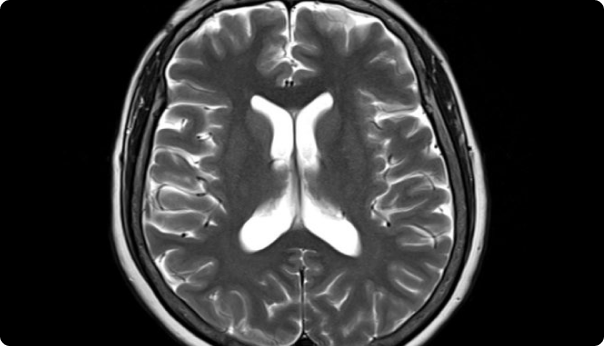

성베드로병원의 MRI 3.0T

MRI(뇌조직)와 MRA(뇌혈관) 촬영 현 최고사양으로 확실하게

성베드로병원의 3.0T MRI는 압도적인 해상도로 뇌 실질의 병변부터 미세 혈관의 흐름까지 한 번에 명확히 찾아냅니다.

MRI

치매, 뇌종양, 뇌경색 등

뇌조직의 정밀 진단